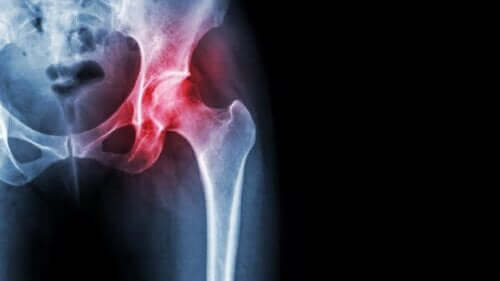

Hauptsymptome einer Kiefernekrose sind freiliegender, nicht therapierbarer Knochen, der auch nach Wochen (sechs bis acht Wochen) nicht abgeheilt ist. Radiologisch sieht man im Knochen Sequesterbildungen und Frakturen im

Unter einer Kiefernekrose versteht man eine Erkrankung, bei der Teile des Kieferknochens nach Medikamentgabe oder Bestrahlung absterben. Als Kiefernekrose bezeichnet man eine Aufweichung und Zerstörung eines